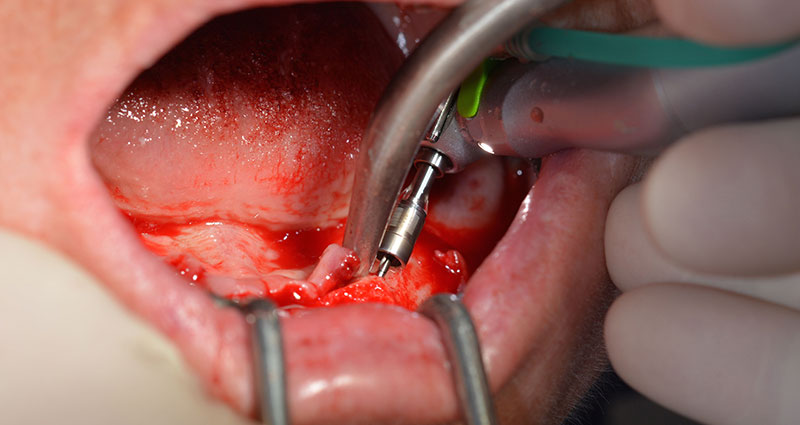

След отстраняване на частичното обеззъбяване в долната челюст, алвеоларният гребен е разкрит от 37 до 47.

Изходът на долночелюстния нерв е първоначално идентифициран като ограничена анатомична структура и, след това, кортикалната кост на гребена е загладена с прав наконечник и голям борер с розовиден профил  (Фиг. 4).

частично обеззъбяване

Фиг. 4